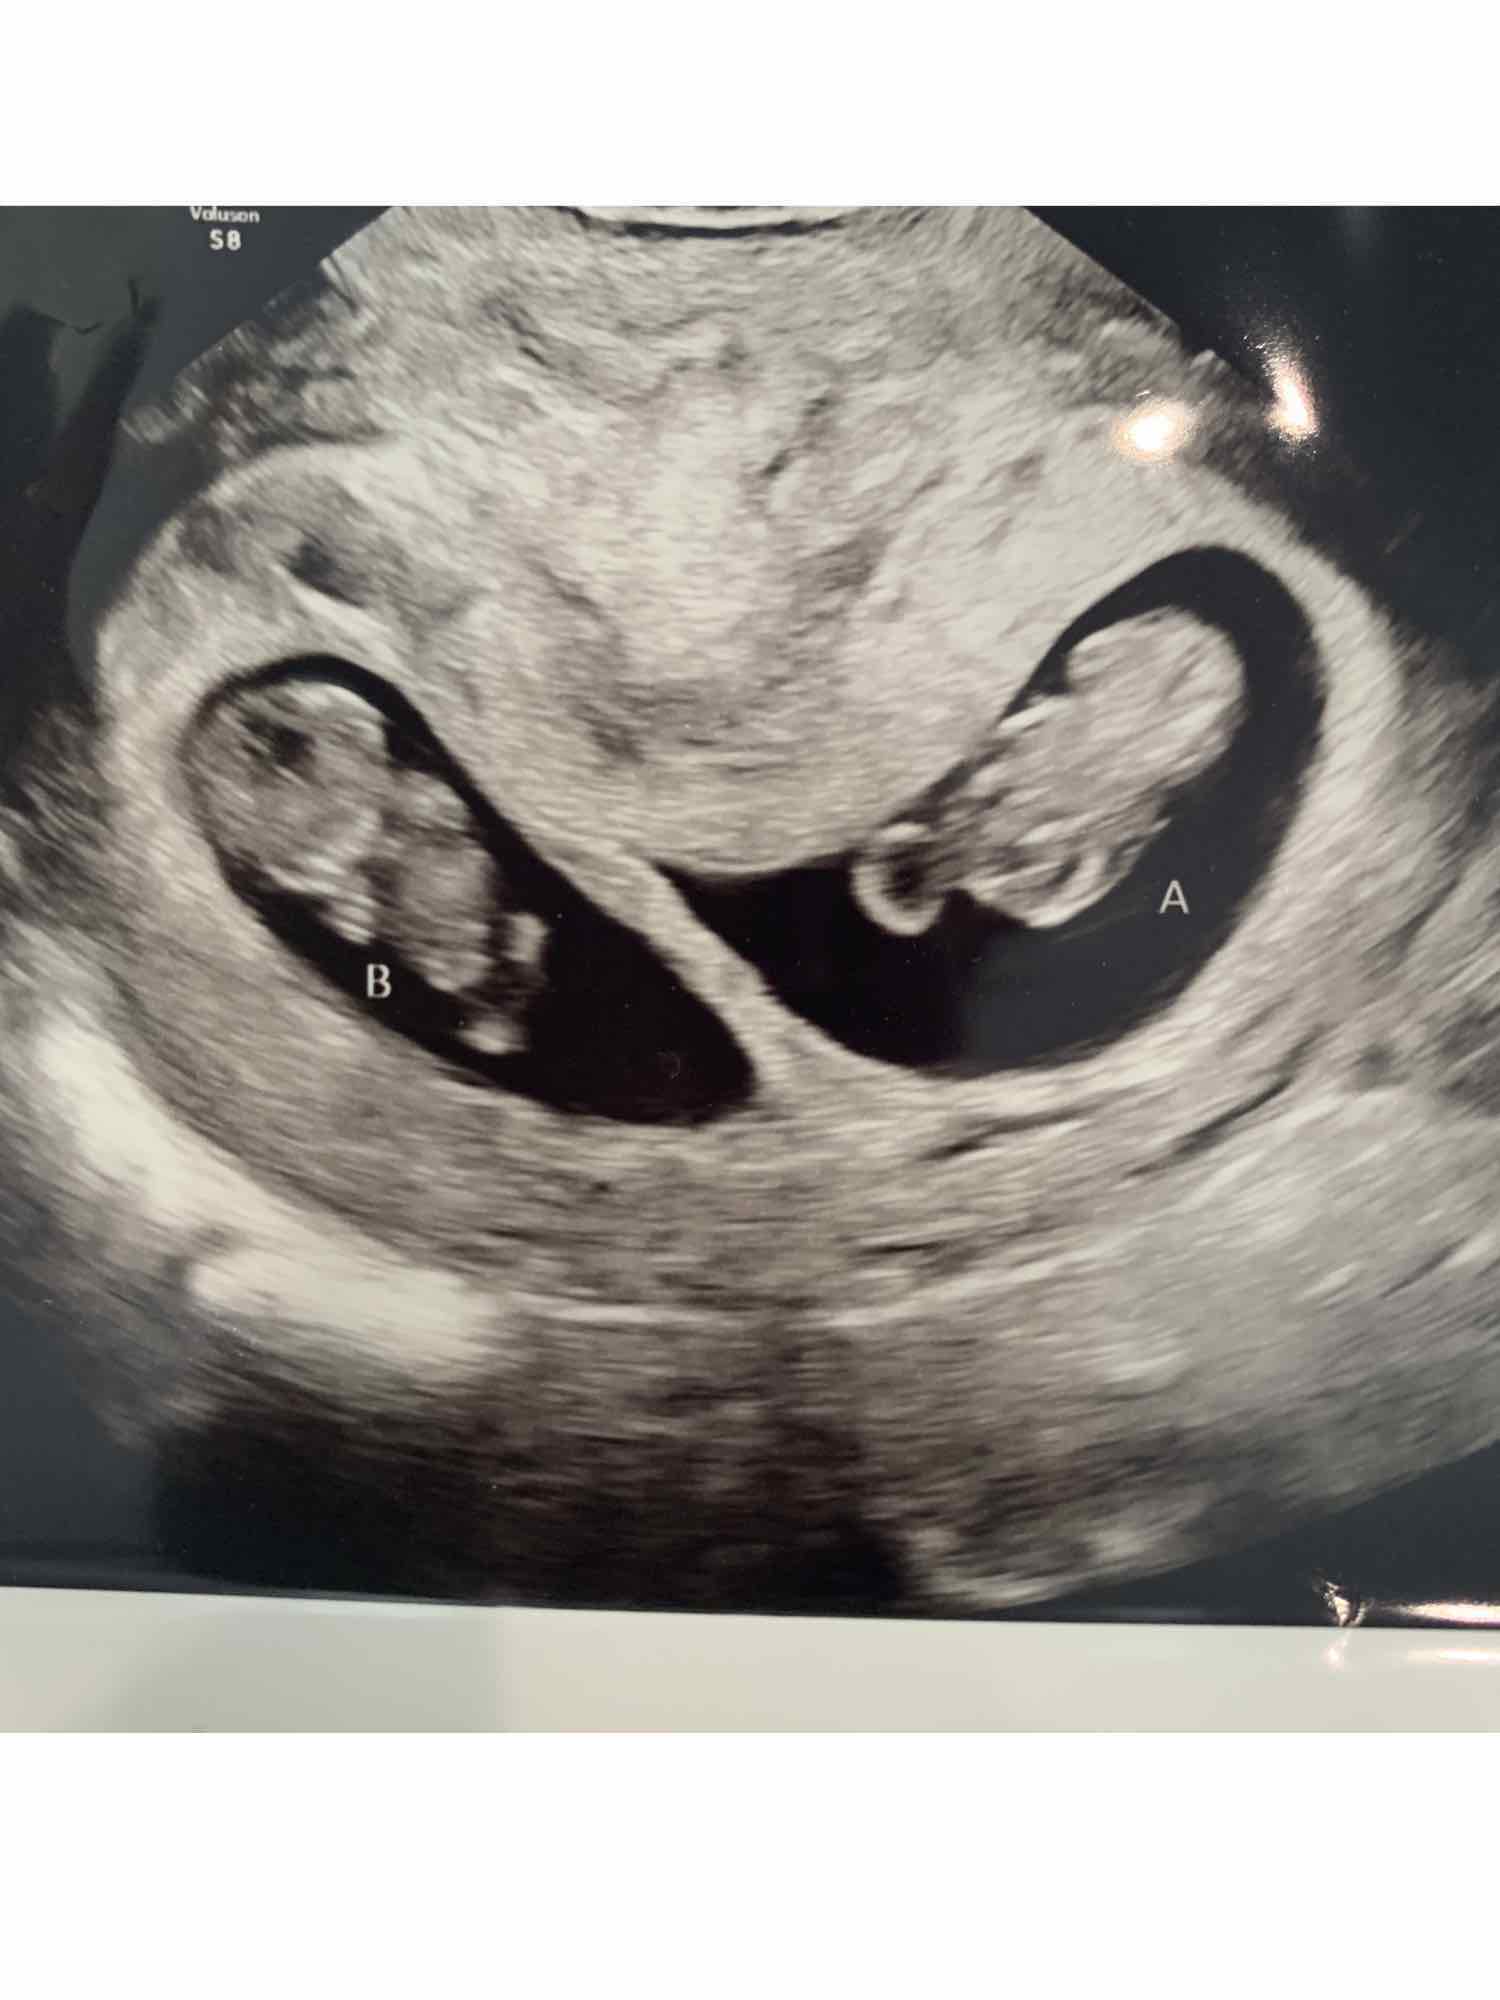

More pictures from my 9w3d dating scan (transvaginal). What do you think... two placentas or one? And any gender hints? Thanks! :)

Attachment 42655

Attachment 42656

Attachment 42657